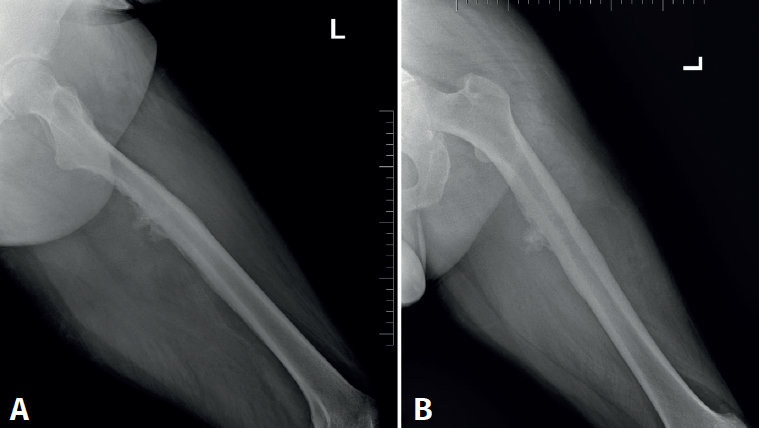

Se trata de un varón de 57 años, empleado en recogida de basura. Diez días antes de la consulta sufre una caída accidental con dolor intenso en el miembro inferior izquierdo, hipoestesia en calcetín y debilidad para la flexión y extensión del tobillo. En la exploración física presentaba Lasègue izquierdo negativo, derecho positivo a 50° y femoral stretch test derecho positivo. Se constató fuerza 1/5 en el tobillo izquierdo. La resonancia magnética (Figura 1) mostró discopatía L4-L5 con hernia discal posteromedial derecha. La electromiografía (EMG) evidenció afectación radiculoplexular izquierda moderada L3-L4 y grave L5-S1 posganglionar.

retla.08216.fs2508016-figura1.png

Figura 1. Resonancia magnética lumbar inicial. A: corte sagital en secuencia T2: discopatía de grado IV en L4-L5 con hernia discal extruida; B: corte axial en secuencia T1 a nivel de L4-L5, con estenosis del receso lateral derecho secundaria a extrusión discal; C: corte axial en secuencia T2, con protrusión discal difusa con estenosis foraminal bilateral y canal medular estrecho (grado C según Schizas-Theumann).